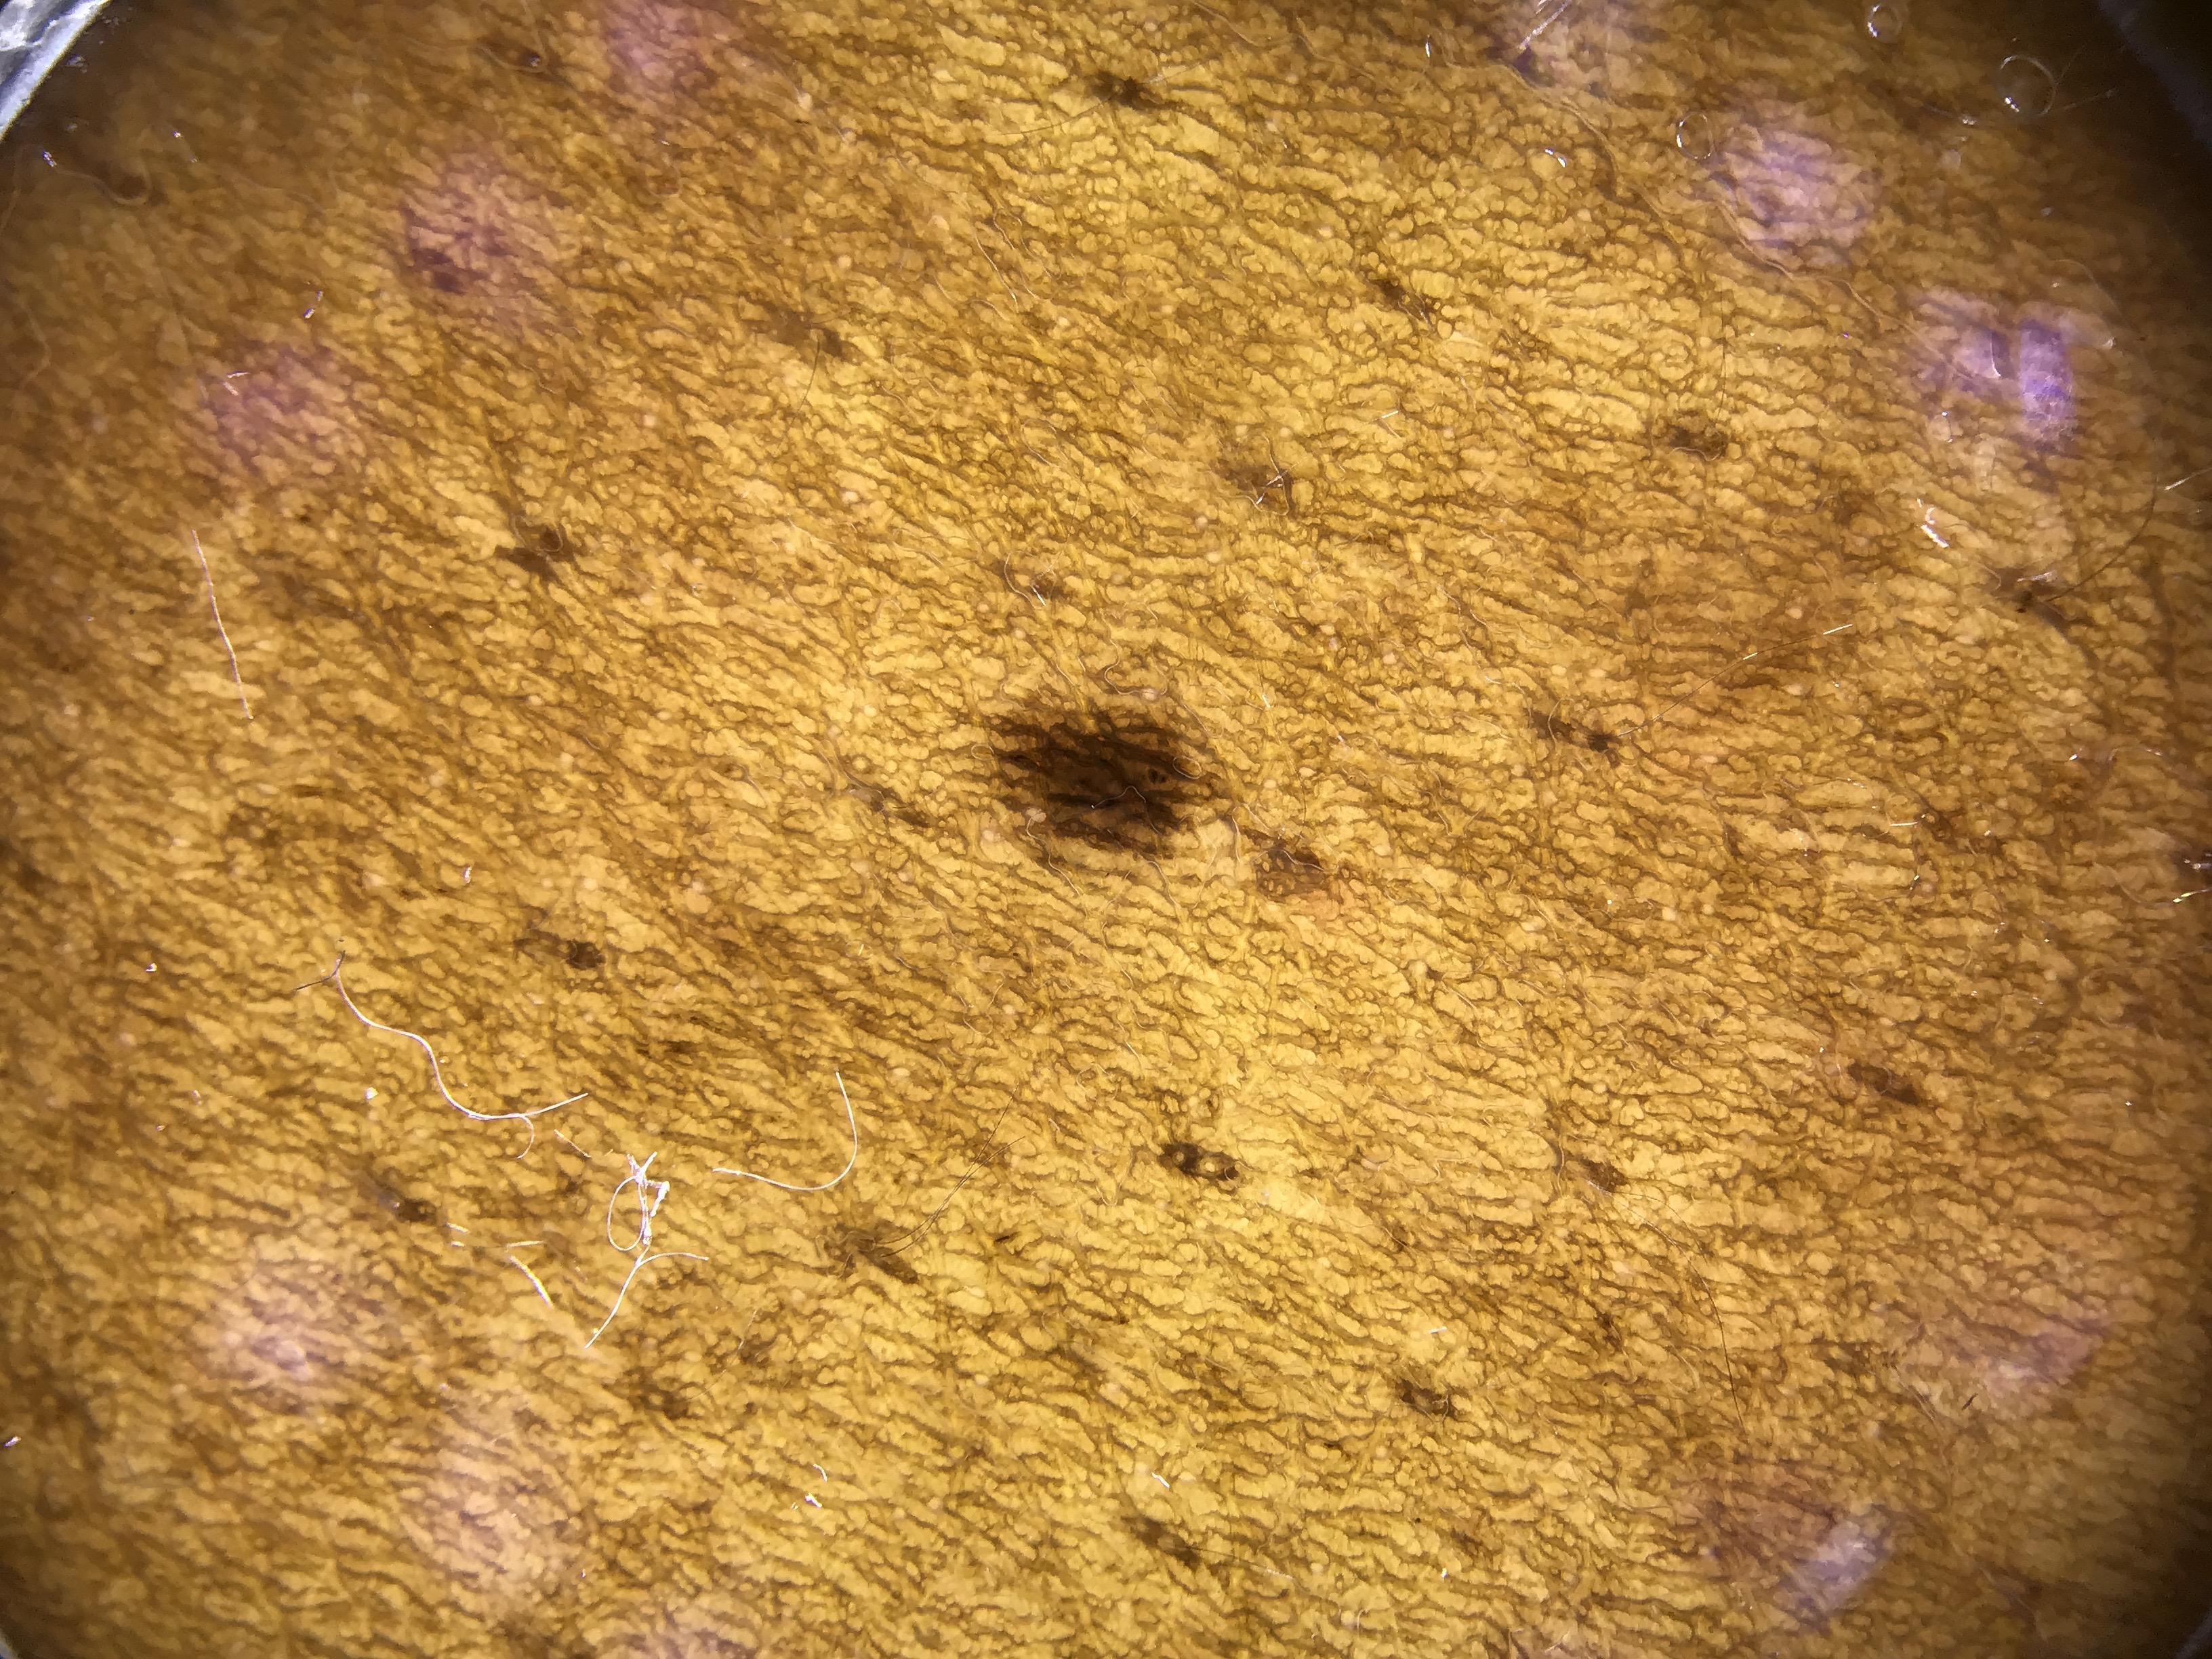

ISIC_0681774

age_approx 55

anatom_site_1 Head and neck

dermoscopic_type contact polarized

diagnosis_1 Benign

diagnosis_confirm_type single contributor clinical assessment

fitzpatrick_skin_type VI

image_type dermoscopic